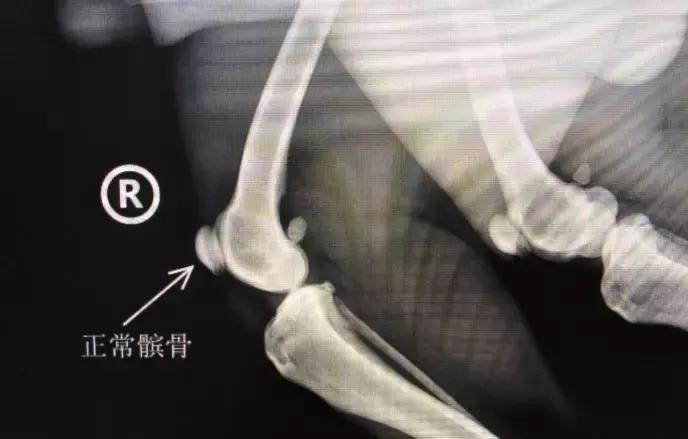

这块骨头的名字叫髌骨,也称膝盖骨。是股四头肌肌腱中形成的一块籽骨,能够上下左右的移动,对关节起保护作用,与股骨,也就是大腿骨的滑车构成关节,一般就在股骨的滑车沟中,如果脱离了这个位置,这种情况就叫做脱位。

了解了什么是髌骨和髌骨脱位的等级后,再看看,到底什么是髌骨脱位?

髌骨脱位是指,在运动中,比如散步、奔跑、跳跃的时候,膝关节进行屈伸,让髌骨从滑车沟中脱出。髌骨脱位也分为内脱位和外脱位,常见的情况是内脱位。也分先天脱位和后天脱位。